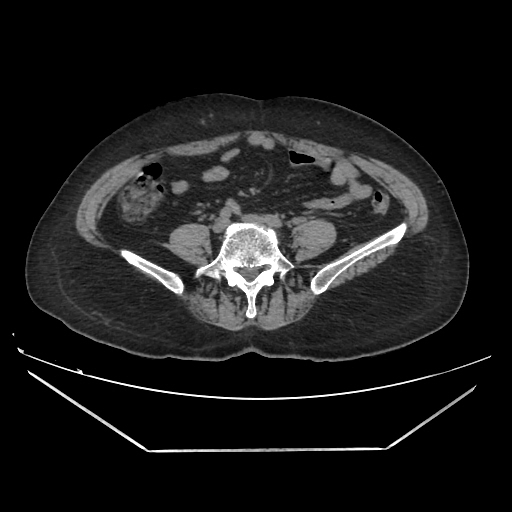

A CT abdomen revealed a left adrenal cortical tumor.

CT images: